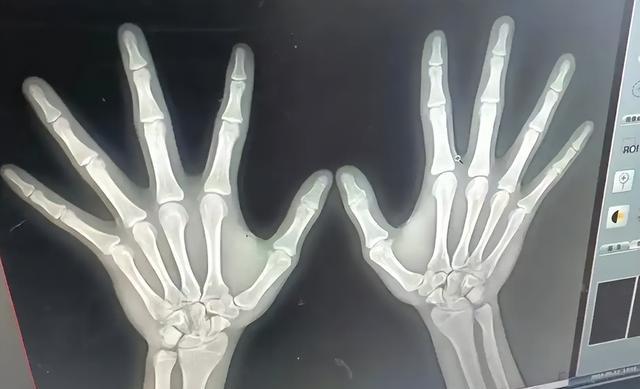

旁边一个爸爸拿着骨龄片,AI系统判了12.5岁,孩子才10岁,医生摇头:预测终身高168,最多170,爸爸当场眼圈红。